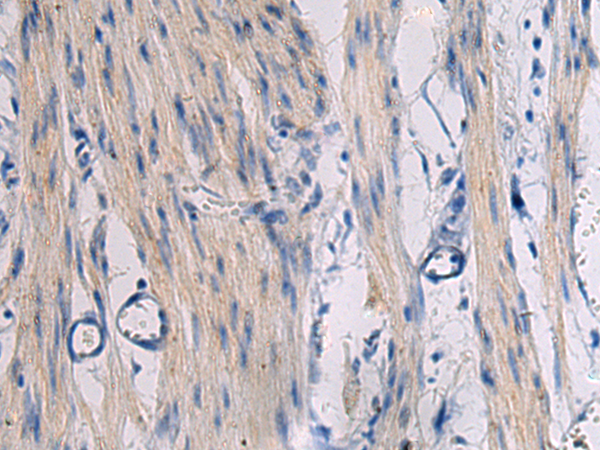

IHC positive control: |

Human esophagus cancer and Human gastric cancer |

IHC Recommend dilution: |

25-50 |